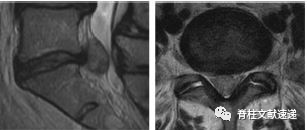

图注:椎间盘囊肿

图注:23岁男性,椎间盘囊肿。术中见波动的椎间盘囊肿并切除。